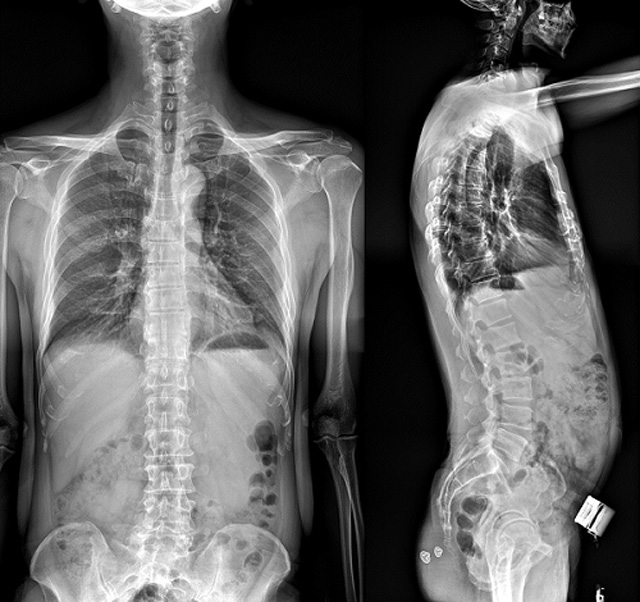

(7)全身拼接功能對有較大尺寸全脊柱拼接圖接桂成金下股分成幾次拍攝,再經(jīng)過秋件開在骨科開展的全脊柱畸形矯治工作中,雖然CT. MRI也能獲取全脊柱影像,接圖像,以便于長度、角度、力線等測量和察脊柱在重力情況下但不能進行立位檢查,無法觀全景觀察。全身拼接功能是高等級DR攝取患者立位全下的功能狀態(tài)圖像,因此采用動態(tài)醫(yī)院特別看重的動態(tài)DR功能之一。注:圖中Cobb脊柱正側(cè)位圖像是首選的檢查方法角度的大小是反映側(cè)彎嚴重程度的一個標準。